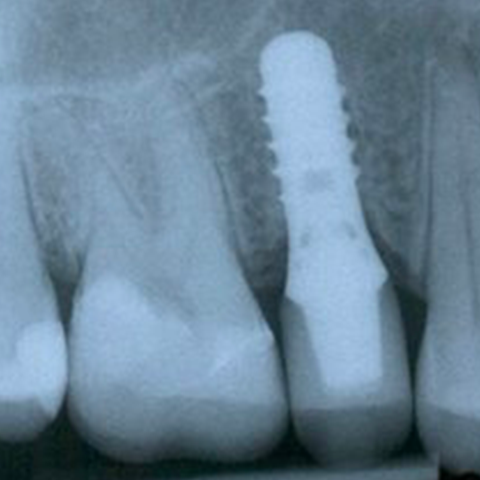

IMPLANTS

Pour remplacer des dents manquantes ou pour faire tenir des prothèses, il est souvent possible d’implanter des racines artificielles en titane dans la mâchoire.